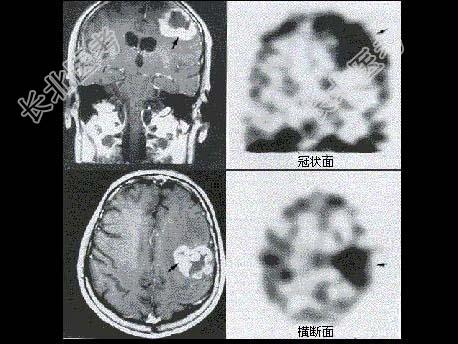

- 单项选择题男性患者恶性脑肿瘤术后6年复查,有放疗病史, 无明显症状,行MRI及99Tcm-ECD脑血流灌注显像, 后者提示局部脑血流减低,行201Tl脑显像如图, 诊断为 ( )

A、箭头示肿瘤脑转移

B、箭头示肿瘤复发

C、箭头示液化坏死区

D、箭头示手术瘢痕形成

E、以上都不是